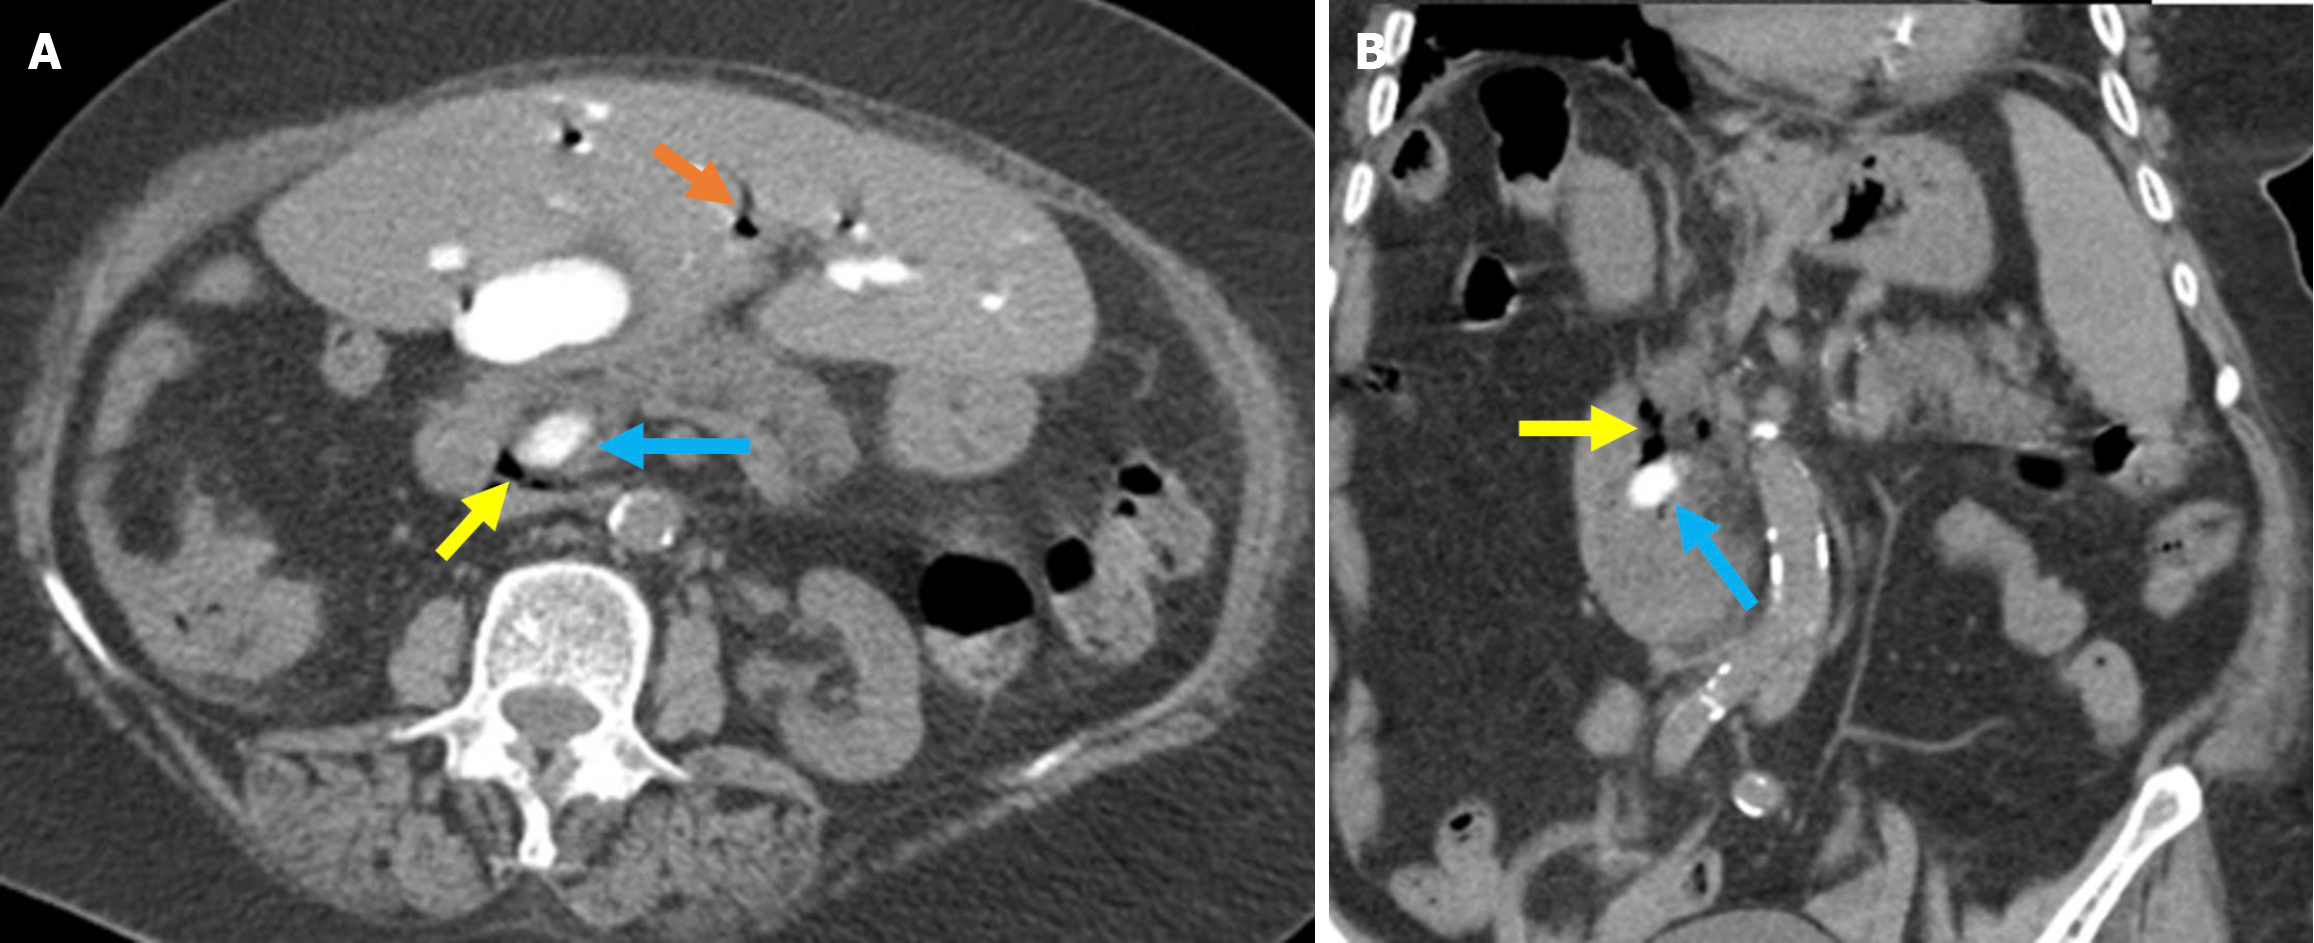

The revised Atlanta classification recognizes two primary forms of acute pancreatitis: NP and interstitial edematous pancreatitis (IEP). NP tends to follow a more severe clinical course with higher rates of infection, organ failure, and mortality. Imaging reveals hypoperfused or non-enhancing areas indicating NP or peripancreatic necrosis. Early collections (within 4 weeks) are referred to as acute necrotic collections. Once encapsulated after 4 weeks, they are known as walled-off necrosis (Figure 3)[23]. IEP is characterized by a diffusely enlarged pancreas with homogeneous enhancement on CECT imaging without areas of necrosis and with peripancreatic fat stranding and fluid accumulation. Fluid collections observed within the first 4 weeks are termed acute peripancreatic fluid collections, while those persisting beyond 4 weeks are classified as pancreatic pseudocysts (Figures 4 and 5).

Figure 4

Figure 4 Interstitial edematous pancreatitis and acute peripancreatic fluid collections. A-C: Contrast-enhanced coronal and axial computed tomography (CT) images (A and C), coronal T2-weighted magnetic resonance imaging (B); D: Fat-suppressed axial T2-weighted magnetic resonance imaging. The 81-year-old female patient diagnosed with post-endoscopic retrograde cholangiopancreatography pancreatitis had presented with epigastric pain and elevated amylase and C-reactive protein levels. CT images showed preserved pancreatic enhancement that was consistent with the absence of necrosis and peripancreatic fat stranding (blue arrow). The pancreatic enlargement and increased T2 signal intensity were suggestive of edema (purple arrow). The pancreas also exhibited mildly diffuse, lace-like T2 hyperintensity within the parenchyma that was associated with a small acute peripancreatic fluid collection (yellow arrow).

Figure 5

Figure 5 Acute peripancreatic fluid collections and pseudocyst. A: Noncontrast axial computed tomography (CT); B: Contrast-enhanced axial CT after 15 months. A 28-year-old female patient underwent endoscopic retrograde cholangiopancreatography for choledocholithiasis. Ten hours after the procedure, the patient developed severe upper quadrant abdominal pain accompanied by fever. No signs of peritonitis were observed, and there was no evidence of hemodynamic instability. Laboratory tests revealed elevated levels of pancreatic enzymes and inflammatory markers. Due to suspected pancreatitis a noncontrast CT performed on post-procedure day 1 (A) demonstrated fluid loculation in the infrahepatic and paraduodenal region that was consistent with acute peripancreatic fluid collections (yellow arrow). The patient was diagnosed with post-endoscopic retrograde cholangiopancreatography edematous pancreatitis and was managed conservatively. A follow-up contrast-enhanced CT performed 1.5 months later (B) showed fluid collection in the exact location with pseudocapsule formation that was consistent with a pseudocyst (blue arrow).